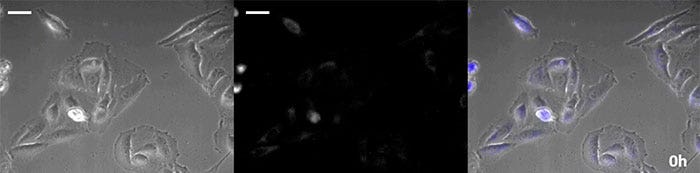

코엘렌테라진형 루시페린은 특히 휘도가 높지만, 짧은 시간 내에 세포 내에서 산화되기 때문에 장기간의 관찰 용도로 사용하려면 적시에 첨가하는 것이 매우 중요합니다.이 문제를 해결하기 위해 고강도 발광 단백질로 세포를 관류하고 자동 기질 첨가 장치가 자동으로 코엘렌테라진을 추가하여 발광을 지속적으로 모니터링할 수 있도록 했습니다.그 결과 위상차 이미징과 함께 발광 이미지를 24시간 이상 모니터링하는 데 성공했습니다(그림 4).

0시간

그림 4-1 0시간

발광 이미지

발광 이미지(파란색)

동영상 2.초파리 배아 발광 이미징(스케일 바: 500µm)